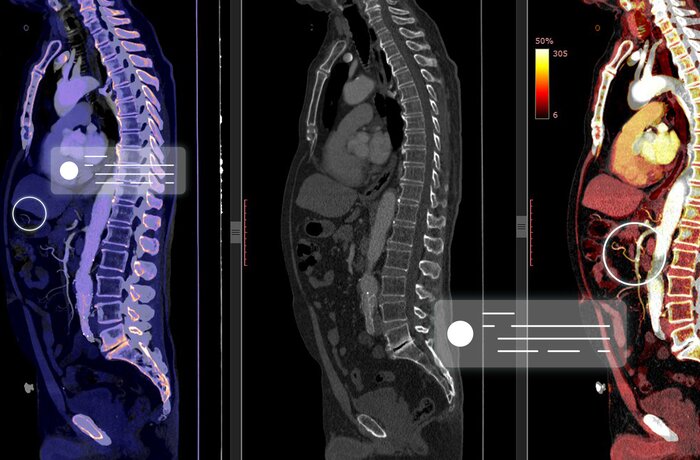

تتميز خوارزميات الذكاء الاصطناعي بقدرتها على تفسير جميع أنواع الصور الطبية، بما يشمل الأشعة المقطعية (CT)، وصور الرنين المغناطيسي (MRI)، وصور الموجات فوق الصوتية، والتصوير المقطعي بالإصدار البوزيتروني (PET)، والتصوير الطبي بأشعة جاما (SPECT)، وغيرها الكثير. باستخدام تقنيات مثل تقسيم الصور، والتحليل الكمي للأنسجة، يمكن للذكاء الاصطناعي تحديد المناطق غير الطبيعية التي قد لا يلاحظها اختصاصي الأشعة أو الطبيب.